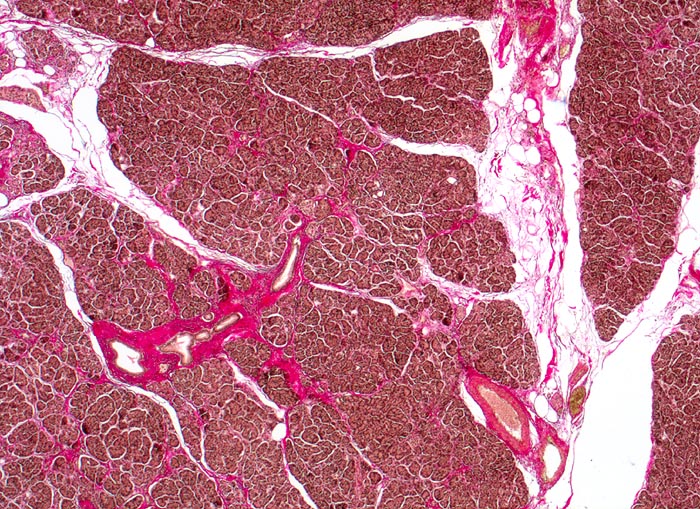

Fast alle exokrinen Drüsen sind betroffen. Pankreasgänge, intestinale Drüsen, intrahepatische Gallengänge und die Glandula submandibularis sind obstruiert durch visköses oder solides eosinophiles Material. Tracheobronchiale und Brunner’sche Drüsen bilden vermehrten Schleim. Schweissdrüsen, kleine Speicheldrüsen und Glandula Parotis sind histologisch normal, sezernieren aber vermehrt Natrium und Chlorid. Veränderungen in der Lunge ( 3689) entwickeln sich als Folge von Luftwegsobstruktion und Infekten (initial vor allem mit Staphylococcus aureus, später meist Pseudomonas aeruginosa).